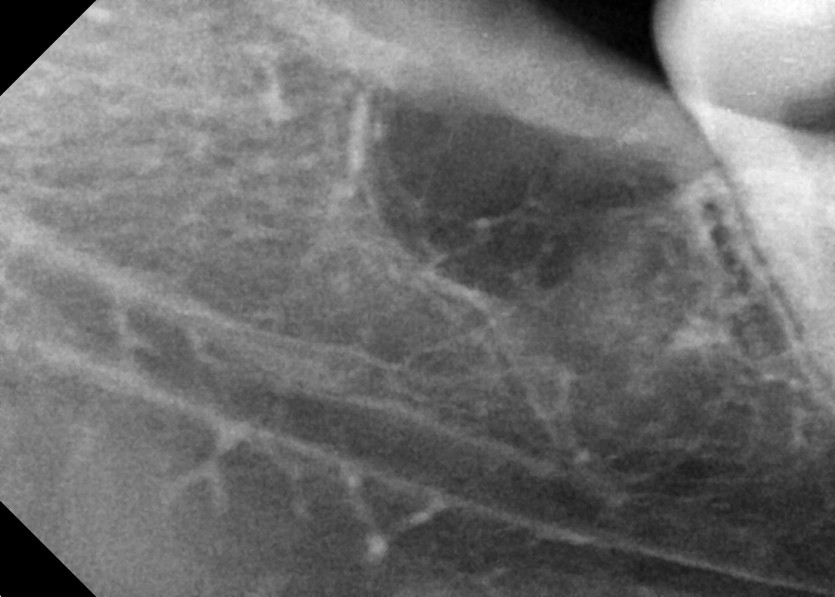

#18,28,38,48 사랑니 발치

구강 외과 전문의가 당일 발치했습니다.